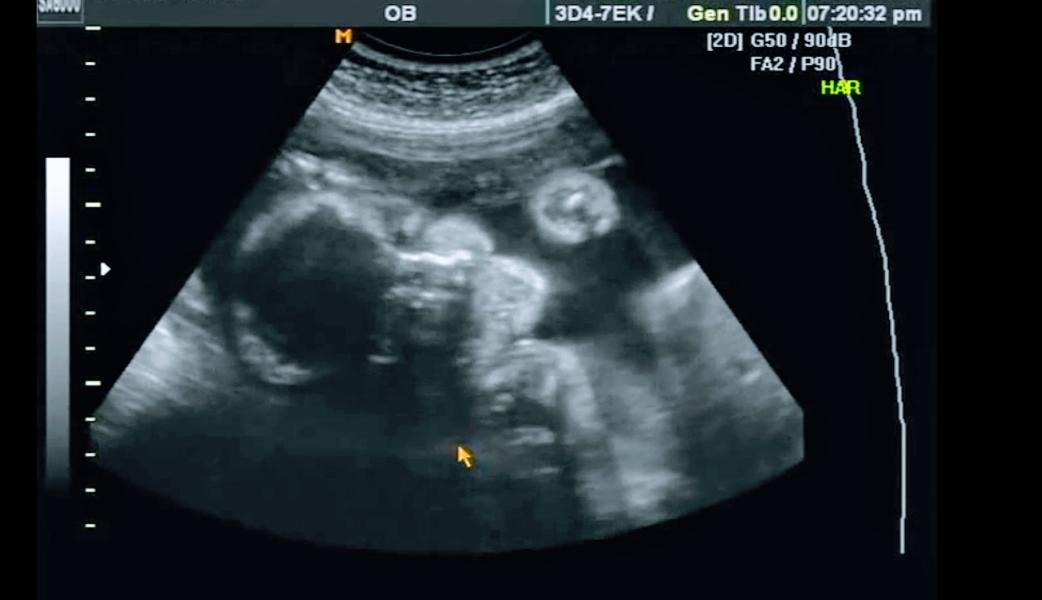

Девочки в пятницу ходила, на узи. Представляете ошиблись, у нас не мальчик будет. А девочка

Я в шоке, нам все говорили мальчик мальчик. А оказывается девочка.